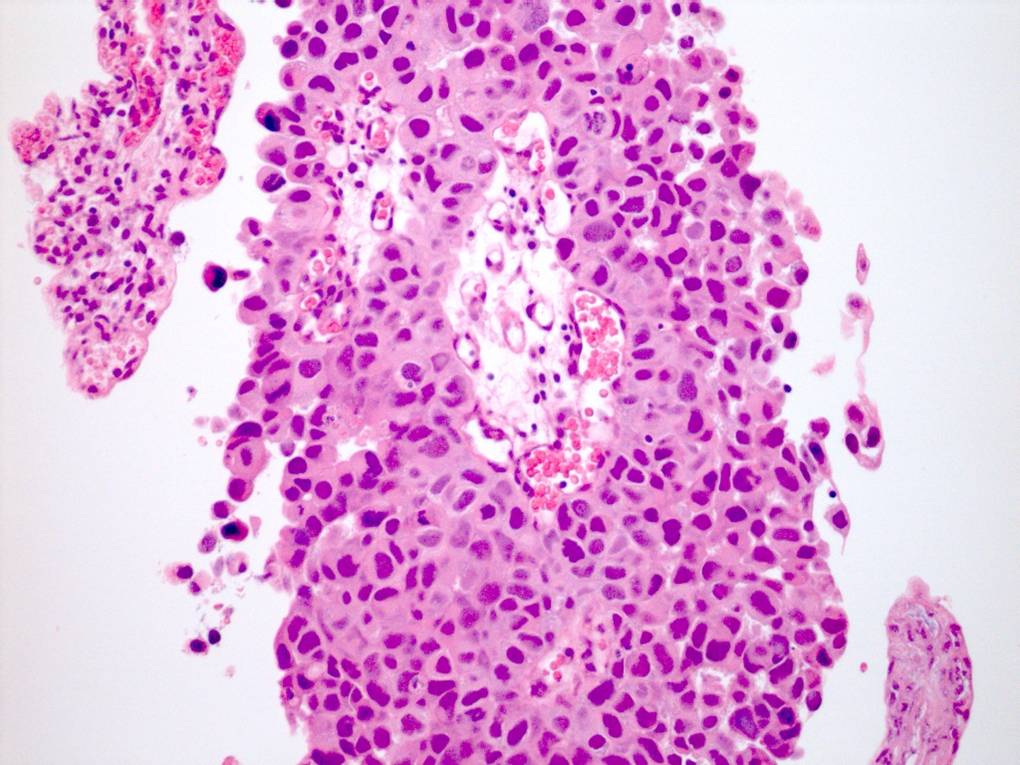

Consensus grade: High-grade papillary urothelial carcinoma (HG-PUC)

Case description (by case creator):

61 year old male. History of haematuria. Diagnosis = high grade papillary urothelial carcinoma with lamina propria invasion.